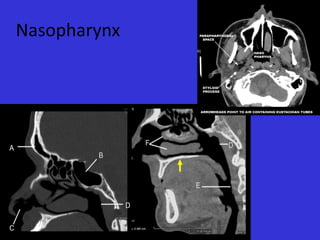

Nasopharynx